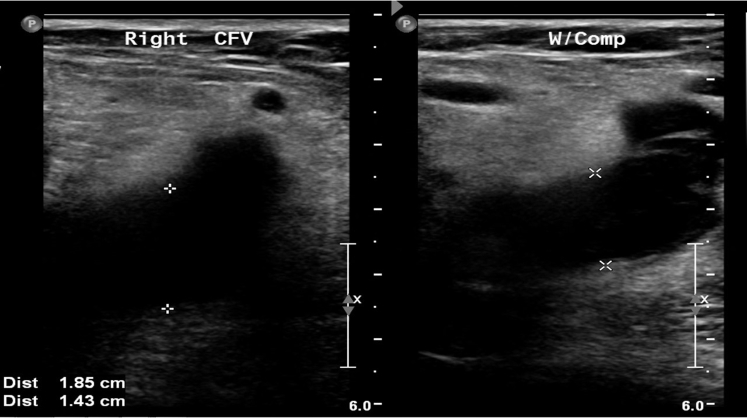

Laboratory evaluation was within normal limits. Diagnostic imaging with venous duplex ultrasound identified extensive occlusive thrombus extending from the right external iliac vein to the infrapopliteal deep veins (Figs 2 and 3).

Fig 2.

Venous duplex ultrasound image of right common femoral vein (CFV) depicting acute dilation, noncompressibility, and hypoechoism. W/Comp, With compression.